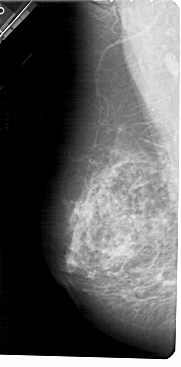

A_1705_1.RIGHT_CC

RIGHT_CC LINES 5491 PIXELS_PER_LINE 2701 BITS_PER_PIXEL 12 RESOLUTION 43.5 OVERLAY